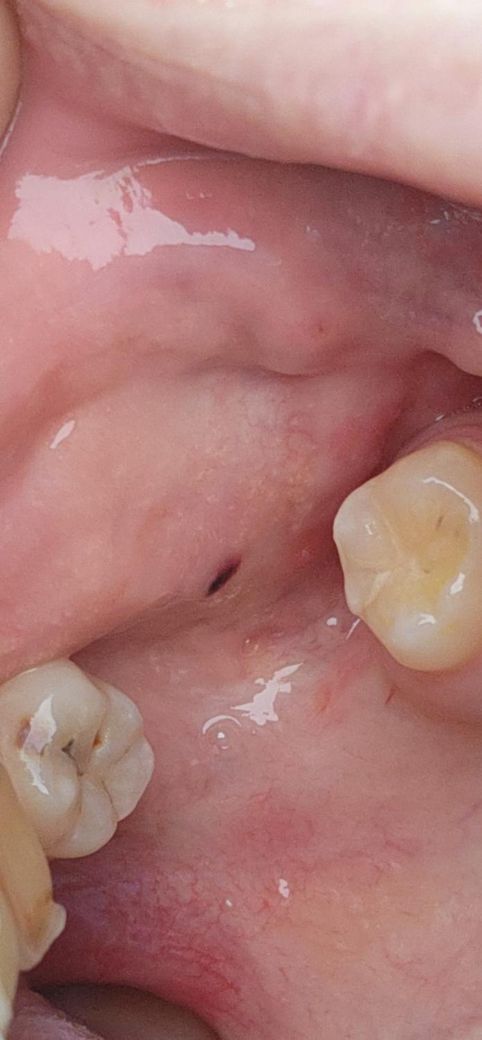

볼 안쪽 입안에 검은점이 생겼는데 큰병 일까요~? (도와주세요 ㅠㅠ)

볼 안쪽 입안에 양쪽으로 검은점이 2개 생긴걸 보게 되었는데 큰병 일까요~? ㅠㅠ..

• 1번 째 사진

-> 볼을 씹어서 혈종이 생긴 듯 합니다.

사진에 보이는건 볼살이 치아에 씹히면서 피가 뭉쳐서 생긴겁니다. 그냥 터트리면 괜찮아 지는겁니다.

사진으로 봤을 경우에는 혈종을 보입니다 점막조직에 손상이 가해지고 점막내부에 출혈이 되면 생기게 되는데 혀종은 자연적으로 없어지기 때문에 너무 걱정하지 않으셔도 됩니다.

구강 내 흑색반(검은점)의 경우 흑색종으로 악성 종양화 될 가능성도 있으나 정확한건 검사를 해봐야 압니다 구강내과 가서 조직검사해보시기 바랍니다